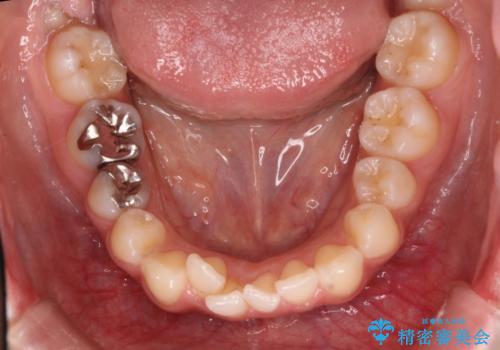

犬歯のねじれ 下の歯のがたがた インビザラインで

- 右上の犬歯のねじれ、下の歯のがたつきを主訴に来院。

下の前歯のがたがたがそれなりにあったため、リファインメントを行いました。